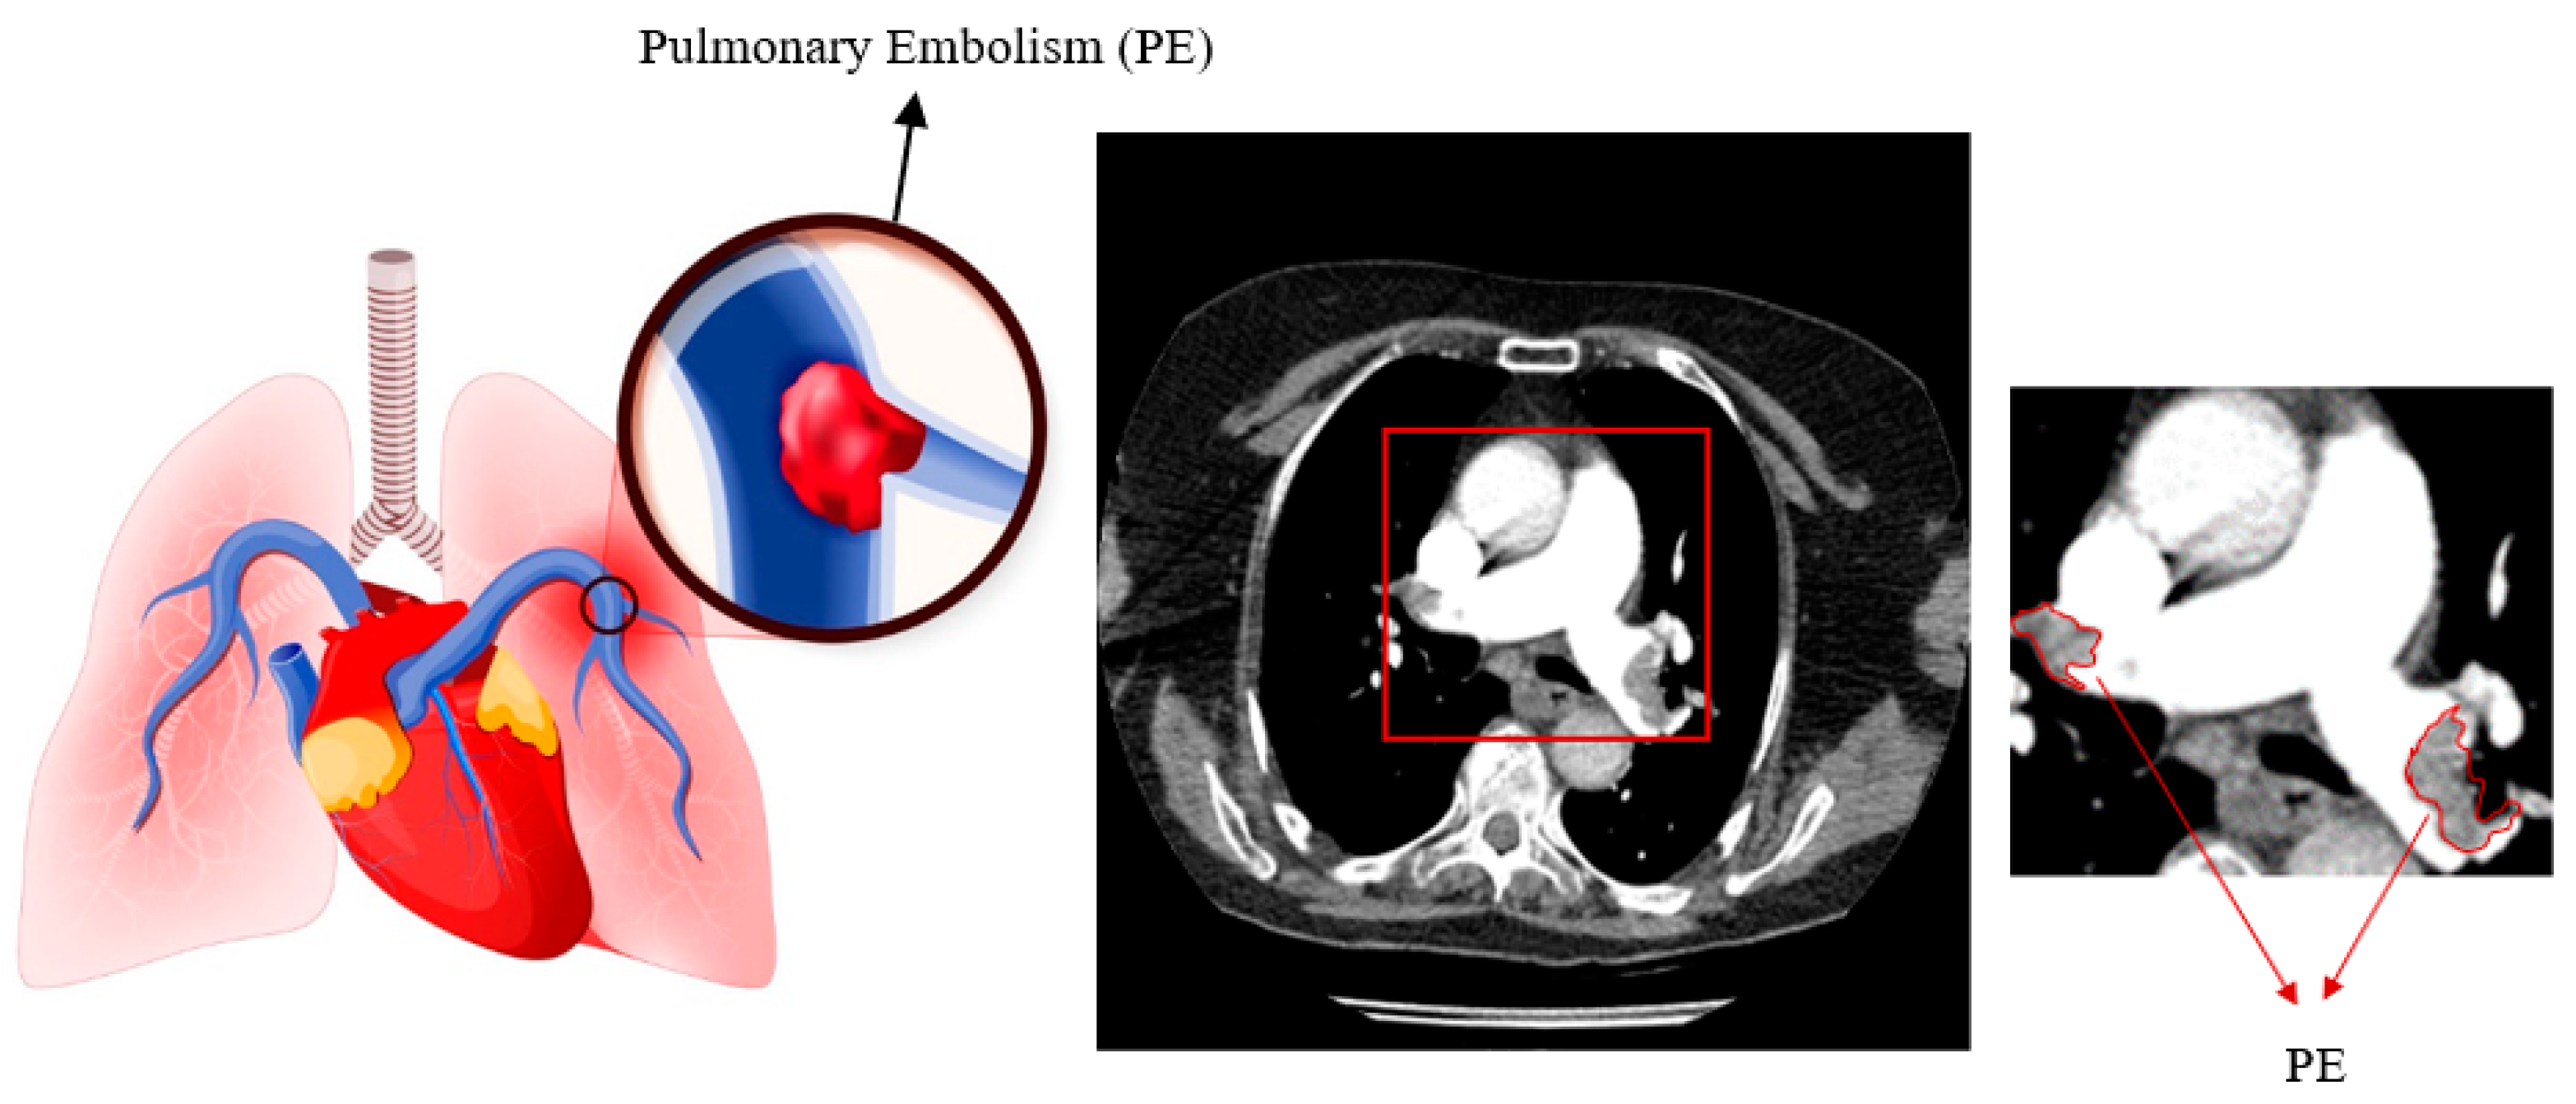

Pulmonary embolism (PE) is the obstruction of blood arteries in the lungs caused by a blood clot[1]. Peripheral edema is third in prevalence among cardiovascular illnesses. The disease has a death rate of 30% [2,3,4]. A delay in diagnosing the condition raises the likelihood of impairment and mortality [5]. Early diagnosis is crucial for treating the disease effectively [6,7]. CTPA is the preferred method for diagnosing PE due to its quick and detailed imaging capabilities [8,9]. Blood arteries show bright on contrast-enhanced CT scans due to the contrast material. The embolism appears dark because it does not absorb the contrast agent. Figure 1 displays pulmonary embolism in a high-quality computed tomography scan.

Figure 1. Representation of Pulmonary Embolism.